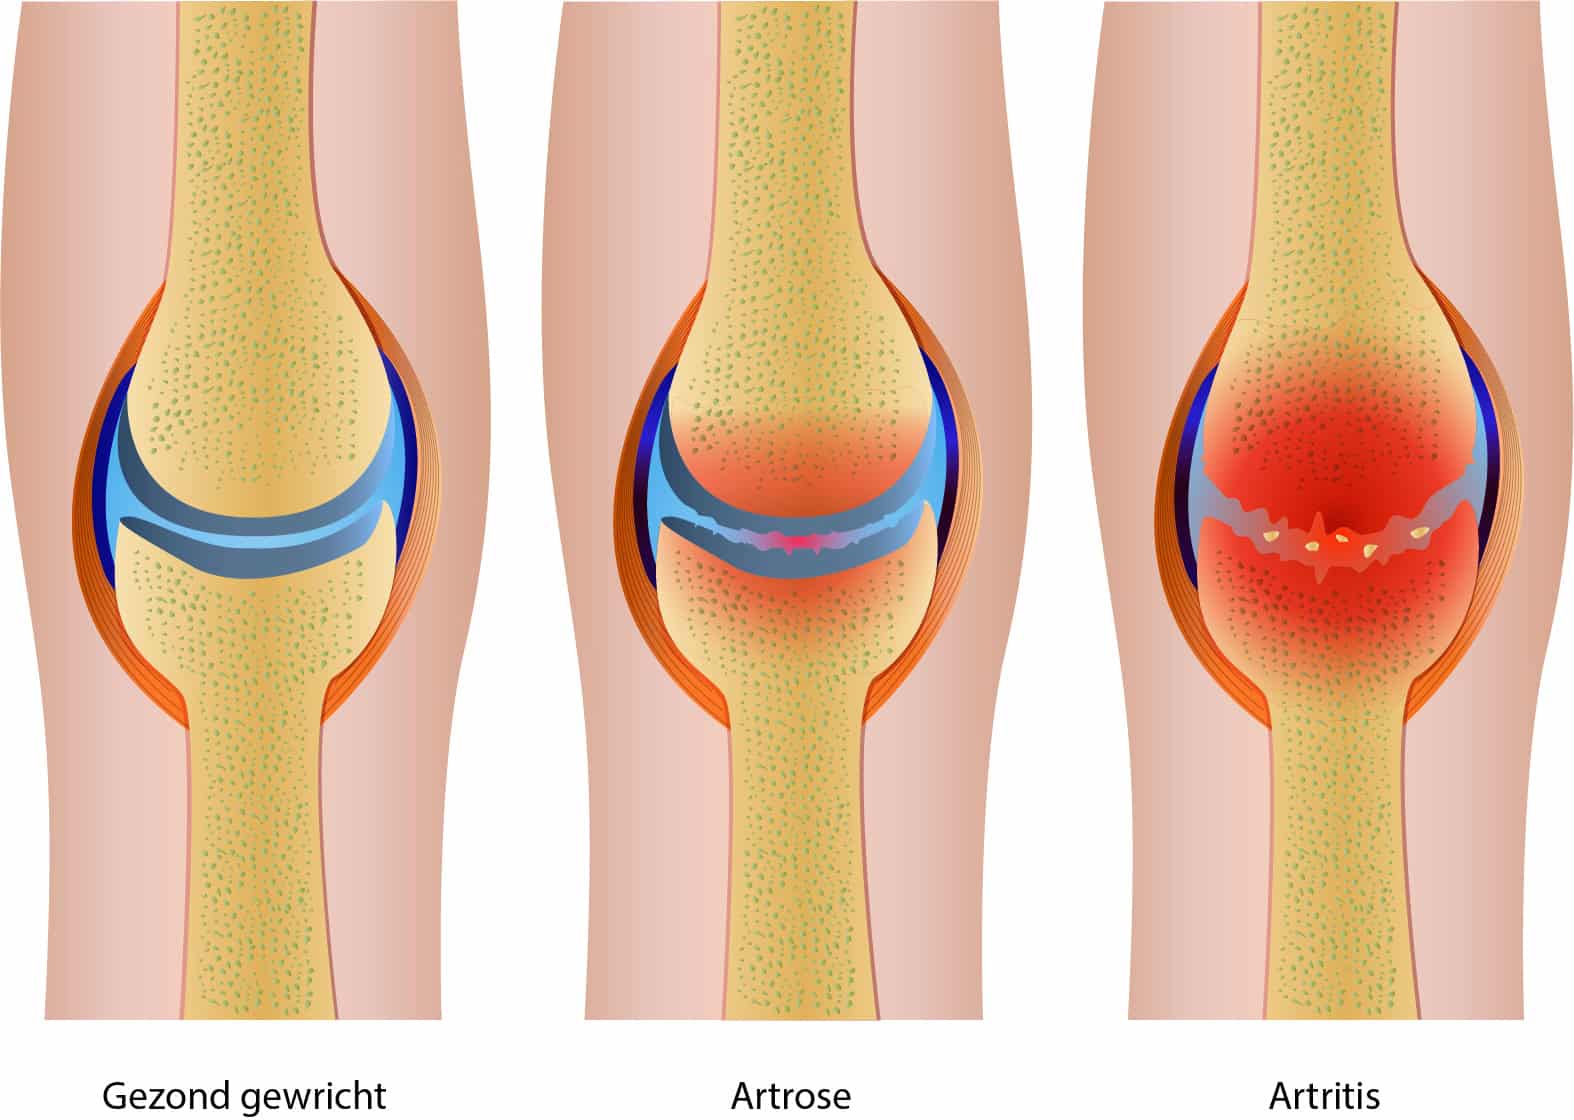

Artrose: Bij artrose is er sprake van slijtage van een gewricht; met name het kraakbeen is hierbij beschadigd, waardoor de botuiteinden dichter tegen elkaar komen te liggen. Het komt veel voor bij ouderen, maar kan ook al op jongere leeftijd optreden. Bij artrose ontstaat er pijn en stijfheid in de gewrichten.

Artritis: Bij een artritis is er sprake van een ontsteking in het gewricht. Een ontsteking in het gewricht heeft drie belangrijke kenmerken: Pijn, zwelling en roodheid. Ook de beweging gaat minder goed (door de pijn en zwelling). Voorbeelden van een gewrichtsontsteking zijn: Jicht, reumatoïde artritis, een opvlamming van artrose of een gewrichtsontsteking door een bacterie.

Afbeelding 2. Artritis en artrose

Alleen is volgens mij bij de afbeelding (2) artritis en artrose omgewisseld.

Thijs (gepromoveerd arts) says:

Scherp! Je hebt helemaal gelijk. Ik heb het plaatje aangepast. Dank je wel!